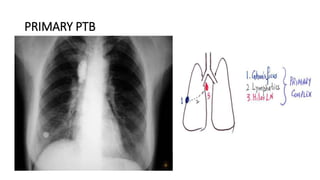

PRIMARY PTB